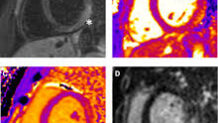

A chest X-ray may show an enlarged heart, fluid in the lungs, or enlarged liver, all suggesting heart failure. Cardiac MRI is increasingly important as it can detect inflammation, tissue characteristics specific to myocarditis, myocardial swelling, and scarring. However, it requires children to lie still for extended periods, often necessitating sedation in younger children.